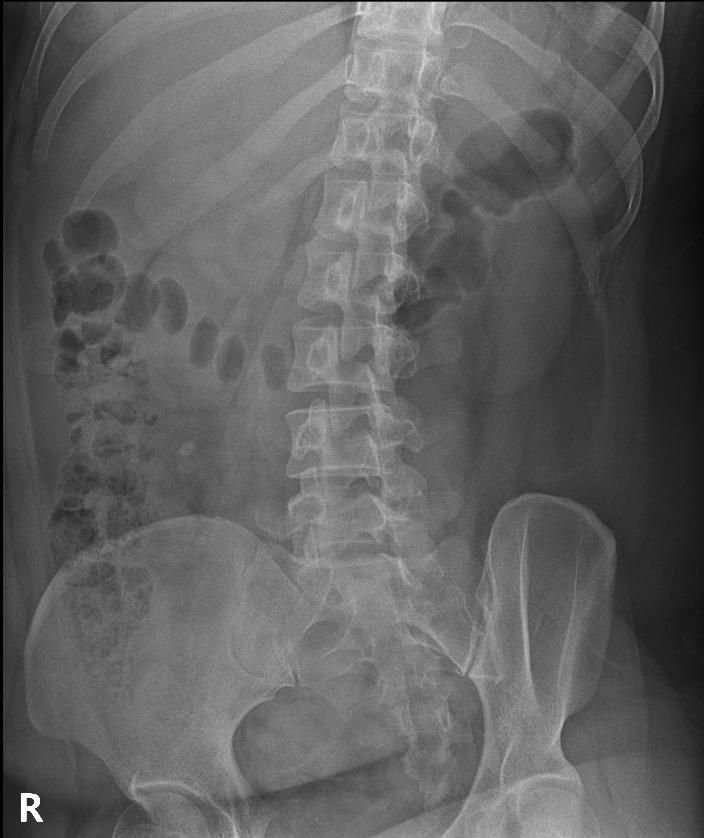

척추분리증인가요??(엑스레이 있어요)

한 병원에서는 척추분리증이라고 하고 한 병원에서는 척추분리증이 아니라고 해서요. 혹시 아래 사진에서 척추분리증 소견이 보이는 사진이 있나요??

여기까지가 a병원에서 찍은 사진이고 아래가 b병원에서 찍은 사진이에요!

• 4번 째 사진

• 5번 째 사진

• 6번 째 사진

척추분리증 맞습니다.

A병원 세번째 사진의 아래 부위에 척추분리증이 있는게 맞습니다.

B병원 사진에서는 비교적 흐리게 보이지만 잘 보면 B병원 엑스레이에서도 같은 부위에 분리증을 확인할 수 있습니다.

두 사진을 비교해서 보았을 때 큰 문제가 있어 보이지는 않으며 엑스레이상 척추분리증 진단이 어렵거나 애매한 경우에는 추가적인 검사 MRI를 통해 진단을 받아보시는 것도 방법이라고 생각합니다.

제가볼때 엑스레이상에 분리증은 보이지않지만 각도에따라 그리고 기계에따라서 달라질수있으니 정확하게 하고싶다면 MRI검사를 추천합니다 감사합니다~

두가지 사진을 비교해보았을 때, 크게 특징적인 것이 관찰되지는 않습니다. 척추분리증을 진단하는 것은 임상증상과 영상검사를 통한 구조적 이상을 확인하는데요, 정확한 검진을 위해서는 ct나 mri같은 검사를 고려하시거나, 척추질환을 전문적으로 진단하는 병원급 의료기관에 방문해보시는 것도 고려해보시면 좋겠습니다.